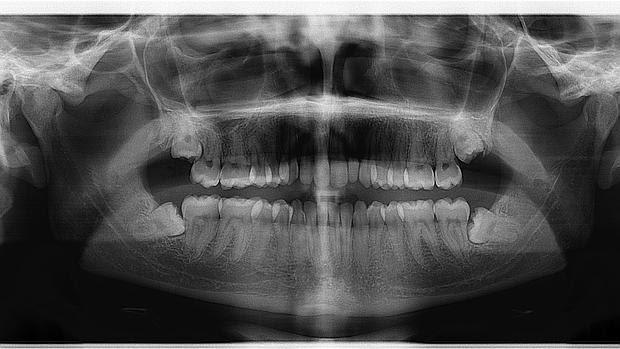

Para llevar a cabo el estudio, los autores evaluaron durante un período de dos años los implantes dentales, 272 en total, de 67 pacientes con 60 o más años de edad a los que sometieron a una radiografía panorámica –u ‘ortopantomografía’–, técnica novedosa que, más barata y sencilla que la tradicional densitometría ósea, permite detectar la posible presencia de osteoporosis y el grado de afectación de la enfermedad a través de la medición de índices morfométricos como el índice cortical mandibular (MCI).

Como explican los investigadores, «es sumamente importante el que a través de una simple ortopantomografía oral se pueda saber el grado de osteoporosis de un paciente, y más aún el corroborar que no es probable que el padecimiento de un cuadro de osteoporosis contraindique la colocación de implantes en los pacientes que lo necesiten».

Así, como explica Guillermo Machuca, coordinador del estudio, «realizamos la radiografía antes, en el momento del implante y dos años después para comprobar si el implante se encontraba en perfectas condiciones o si, por el contrario, se había producido algún tipo de pérdida ósea marginal alrededor de la fijación».